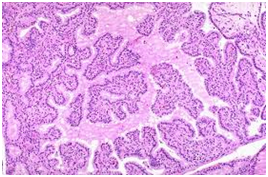

Microscopic interpretation6,4

Additional features are a patchy, variable stromal lymphoid infiltrate. Post therapy colloid accumulation shows peripheral scalloping. Per operative potassium iodide utilized to clamp blood vessels incites epithelial involution with abundant colloid. Per-operative propylthiouracil elicits a florid follicular hyperplasia/hypertrophy. Radioactive iodine initiates dissolution of some follicles, vascular changes, nuclear atypia and stromal fibrosis. Follicular atrophy, fibrosis, nodular architecture and oncocytic change are visualized subsequently. Lympho-plasmacytic infiltrate of the peri-orbital soft tissue and extra-orbital skeletal muscle is perceived. Hyperkeratosis and deposition of acid muco-polysaccharides occurs in the dermis (Figures 2-5) (Table 1).

Figure 3 Graves Disease- Glandular hyperplasia with papillary unfolding.